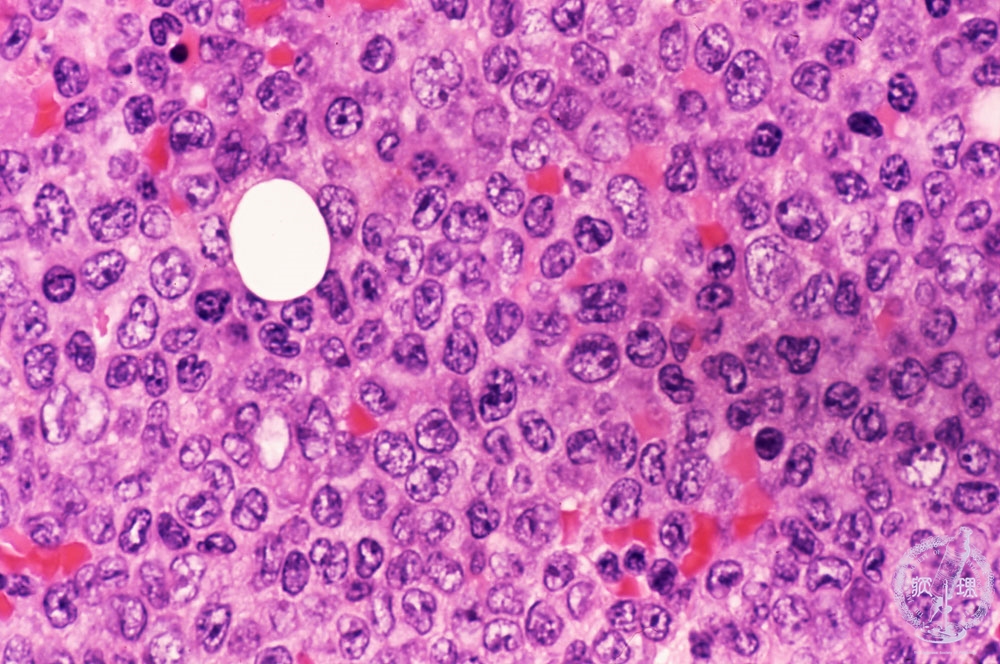

Microscopic image (H&E high power view): Myeloblasts composed of 95% of packed cells. Many of those have kidney-shaped nuclei.